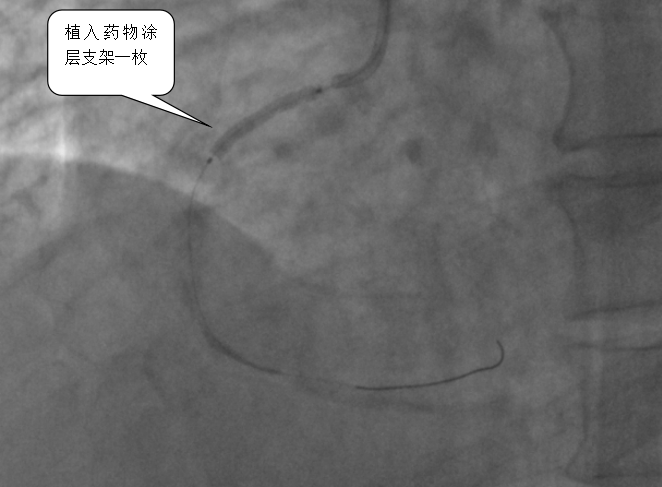

医院心血管内科专家团队立即启动胸痛中心绿色通道,从患者入院到完成心电图检查仅用3分钟,确诊后2分钟内即给予抗血小板治疗,并紧急实施冠脉介入手术。术中造影发现患者右冠状动脉近段完全闭塞,医生通过血栓抽吸、冠脉内溶栓及药物球囊扩张等操作,最终成功植入支架,恢复血流。术后患者血压、心率恢复正常,转危为安。